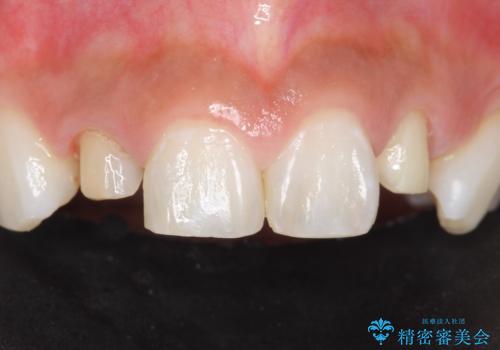

天然歯のような自然な仕上がりに大変喜んで頂けました。

クラウンの種類:オールセラミッククラウン スペシャル

矯正せずに早く治したいという強いご希望により、セラミッククラウンによる補綴治療(上顎両側2の2本)を行いました。